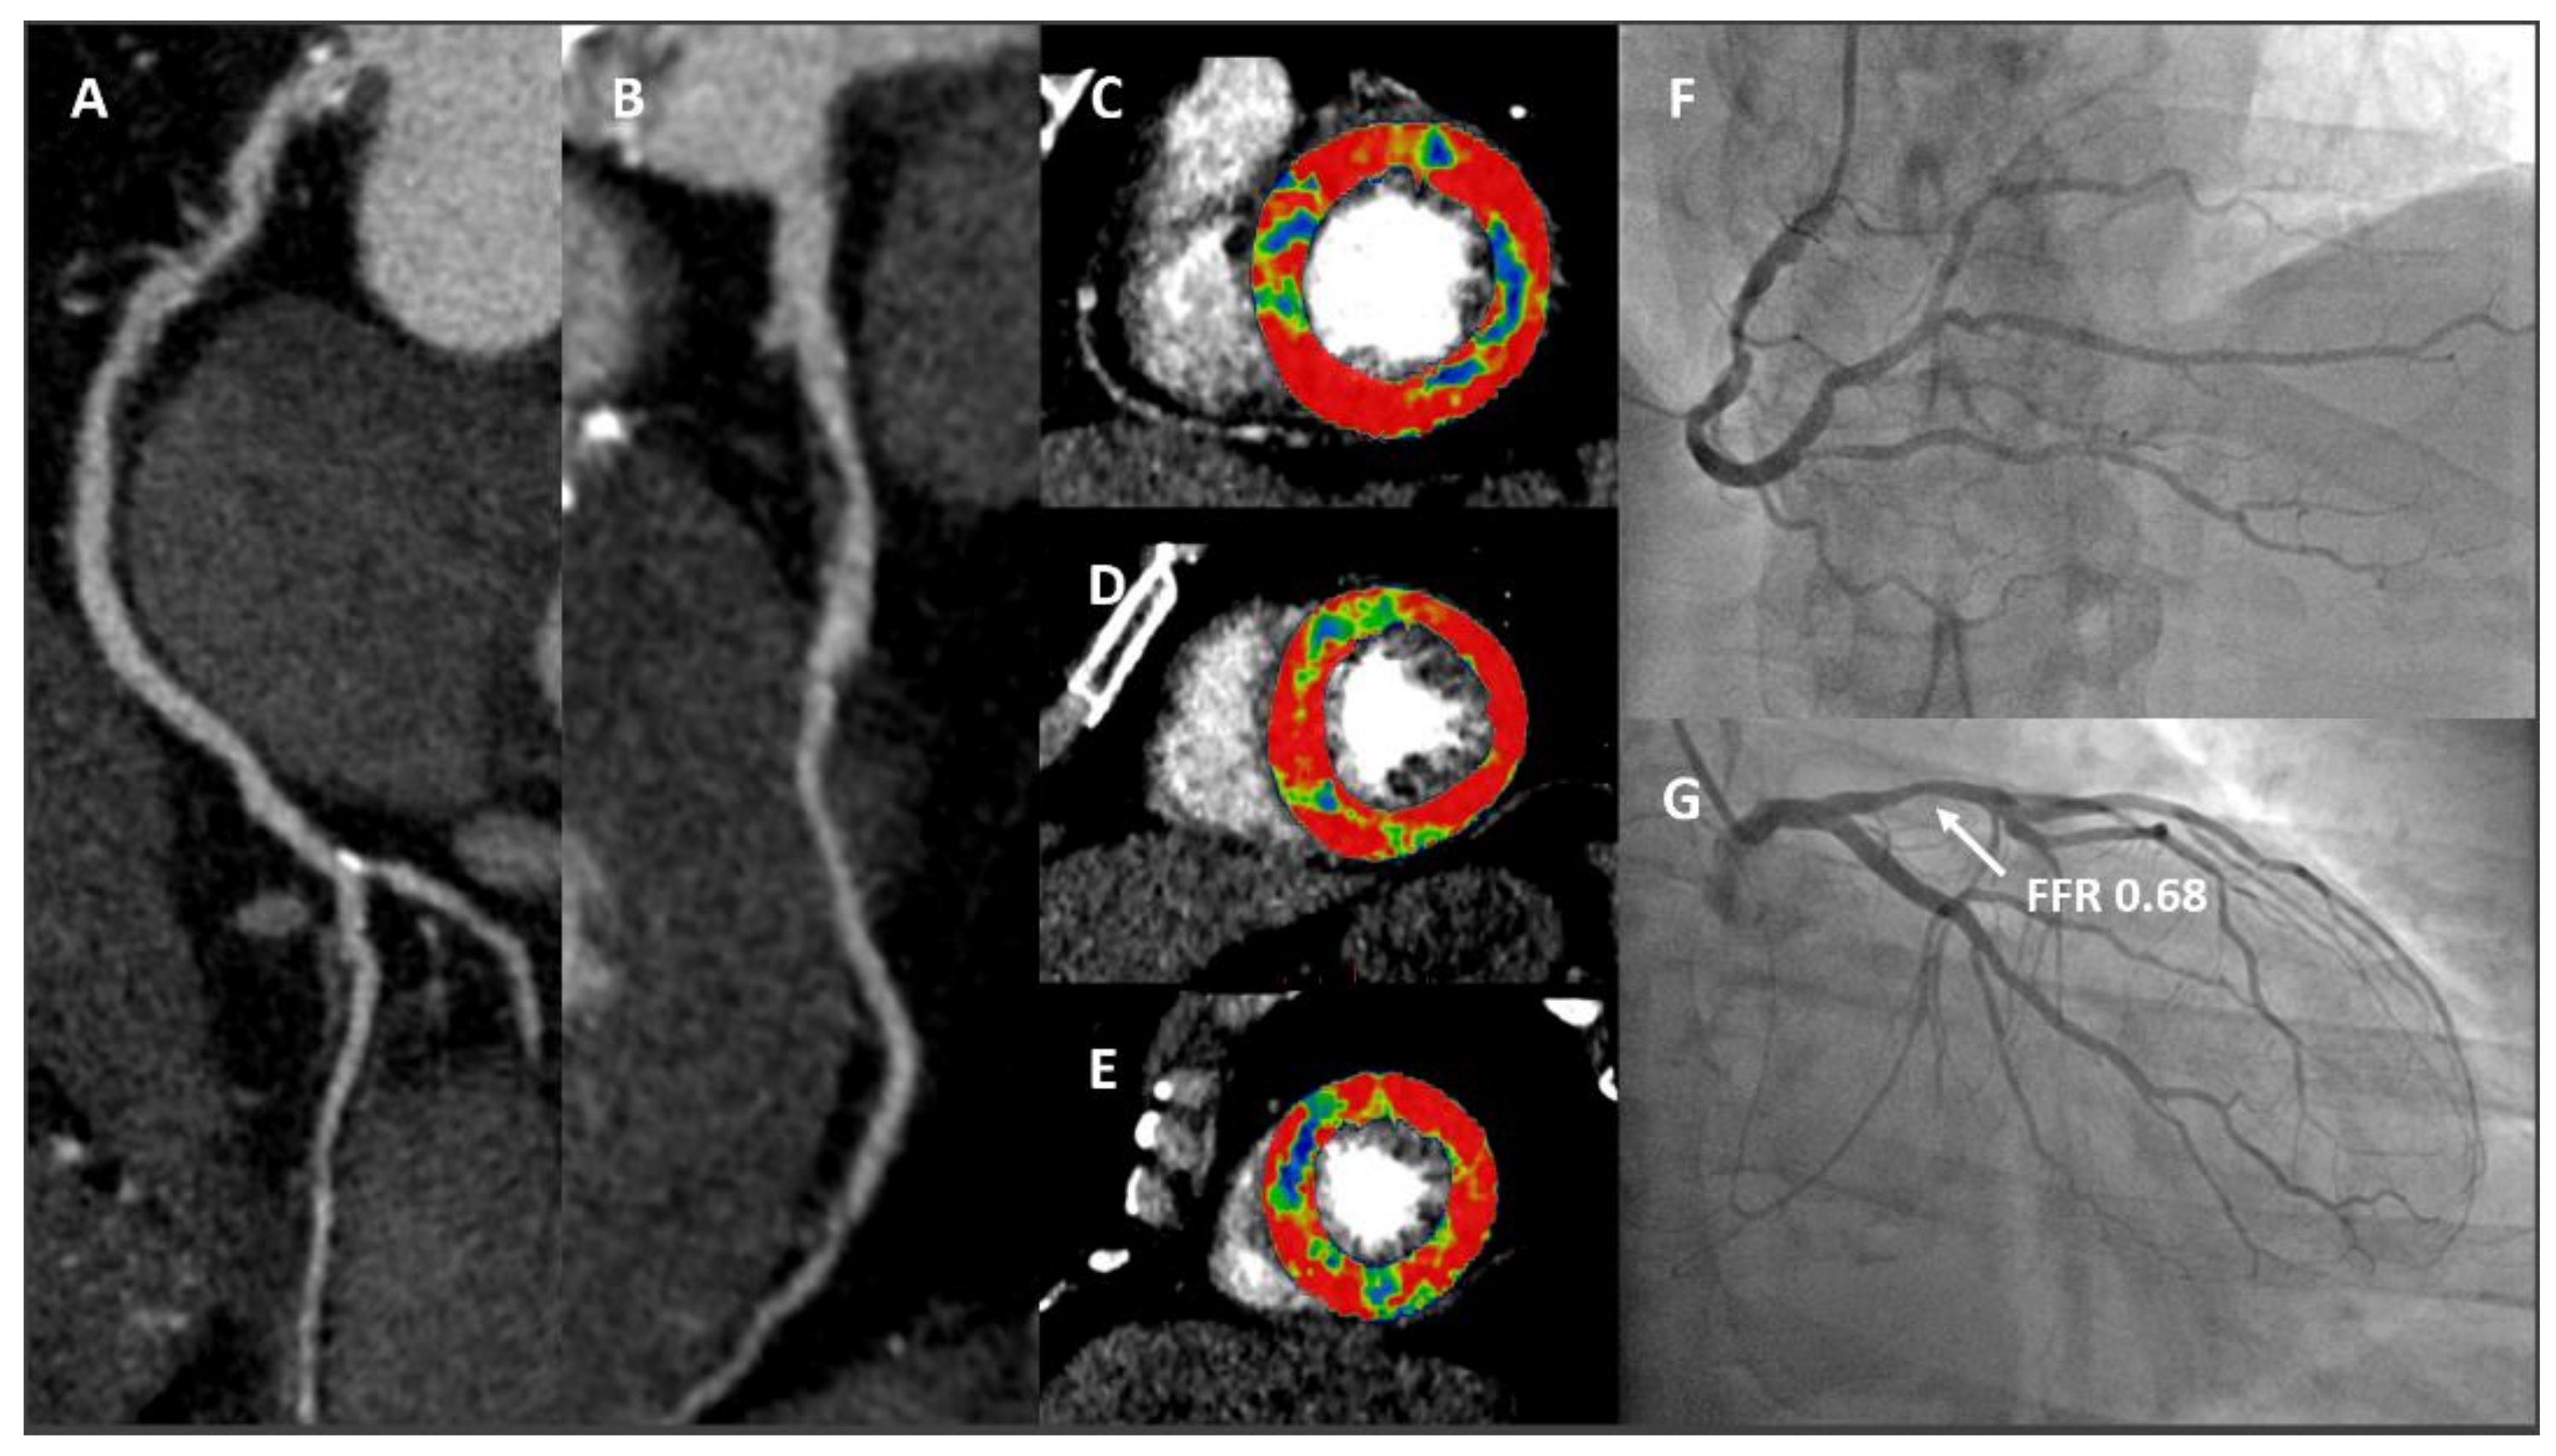

- Taylor, C.A.; Fonte, T.A.; Min, J.K. Computational fluid dynamics applied to cardiac computed tomography for noninvasive quantification of fractional flow reserve: Scientific basis. J. Am. Coll. Cardiol. 2013, 61, 2233–2241. [Google Scholar] [CrossRef] [Green Version]

- Ball, C.; Pontone, G.; Rabbat, M. Fractional Flow Reserve Derived from Coronary Computed Tomography Angiography Datasets: The Next Frontier in Noninvasive Assessment of Coronary Artery Disease. Biomed. Res. Int. 2018, 2018, 2680430. [Google Scholar] [CrossRef]

- Pontone, G.; Muscogiuri, G.; Andreini, D.; Guaricci, A.I.; Guglielmo, M.; Mushtaq, S.; Baggiano, A.; Conte, E.; Beltrama, V.; Annoni, A.; et al. The New Frontier of Cardiac Computed Tomography Angiography: Fractional Flow Reserve and Stress Myocardial Perfusion. Curr. Treat. Options Cardiovasc. Med. 2016, 18, 74. [Google Scholar] [CrossRef] [PubMed]

- Norgaard, B.L.; Leipsic, J.; Gaur, S.; Seneviratne, S.; Ko, B.S.; Ito, H.; Jensen, J.M.; Mauri, L.; De Bruyne, B.; Bezerra, H.; et al. Diagnostic performance of noninvasive fractional flow reserve derived from coronary computed tomography angiography in suspected coronary artery disease: The NXT trial (Analysis of Coronary Blood Flow Using CT Angiography: Next Steps). J. Am. Coll. Cardiol. 2014, 63, 1145–1155. [Google Scholar] [CrossRef] [PubMed] [Green Version]

- Rossi, A.; Merkus, D.; Klotz, E.; Mollet, N.; de Feyter, P.J.; Krestin, G.P. Stress myocardial perfusion: Imaging with multidetector CT. Radiology 2014, 270, 25–46. [Google Scholar] [CrossRef] [Green Version]

- Pontone, G.; Andreini, D.; Baggiano, A.; Bertella, E.; Mushtaq, S.; Conte, E.; Beltrama, V.; Guaricci, A.I.; Pepi, M. Functional relevance of coronary artery disease by cardiac magnetic resonance and cardiac computed tomography: Myocardial perfusion and fractional flow reserve. Biomed. Res. Int. 2015, 2015, 297696. [Google Scholar] [CrossRef]

- Pontone, G.; Baggiano, A.; Andreini, D.; Guaricci, A.I.; Guglielmo, M.; Muscogiuri, G.; Fusini, L.; Soldi, M.; Del Torto, A.; Mushtaq, S.; et al. Diagnostic accuracy of simultaneous evaluation of coronary arteries and myocardial perfusion with single stress cardiac computed tomography acquisition compared to invasive coronary angiography plus invasive fractional flow reserve. Int. J. Cardiol. 2018, 273, 263–268. [Google Scholar] [CrossRef]

- Bamberg, F.; Marcus, R.P.; Becker, A.; Hildebrandt, K.; Bauner, K.; Schwarz, F.; Greif, M.; von Ziegler, F.; Bischoff, B.; Becker, H.C.; et al. Dynamic myocardial CT perfusion imaging for evaluation of myocardial ischemia as determined by MR imaging. JACC Cardiovasc. Imaging 2014, 7, 267–277. [Google Scholar] [CrossRef] [PubMed] [Green Version]

- Pontone, G.; Andreini, D.; Guaricci, A.I.; Baggiano, A.; Fazzari, F.; Guglielmo, M.; Muscogiuri, G.; Berzovini, C.M.; Pasquini, A.; Mushtaq, S.; et al. Incremental Diagnostic Value of Stress Computed Tomography Myocardial Perfusion With Whole-Heart Coverage CT Scanner in Intermediate- to High-Risk Symptomatic Patients Suspected of Coronary Artery Disease. JACC Cardiovasc. Imaging 2019, 12, 338–349. [Google Scholar] [CrossRef]

- Pontone, G.; Baggiano, A.; Andreini, D.; Guaricci, A.I.; Guglielmo, M.; Muscogiuri, G.; Fusini, L.; Soldi, M.; Del Torto, A.; Mushtaq, S.; et al. Dynamic Stress Computed Tomography Perfusion With a Whole-Heart Coverage Scanner in Addition to Coronary Computed Tomography Angiography and Fractional Flow Reserve Computed Tomography Derived. JACC Cardiovasc. Imaging 2019, 12, 2460–2471. [Google Scholar] [CrossRef]

- Lubbers, M.; Coenen, A.; Kofflard, M.; Bruning, T.; Kietselaer, B.; Galema, T.; Kock, M.; Niezen, A.; Das, M.; van Gent, M.; et al. Comprehensive Cardiac CT With Myocardial Perfusion Imaging Versus Functional Testing in Suspected Coronary Artery Disease: The Multicenter, Randomized CRESCENT-II Trial. JACC Cardiovasc. Imaging 2018, 11, 1625–1636. [Google Scholar] [CrossRef]

- Baggiano, A.; Fusini, L.; Del Torto, A.; Vivona, P.; Guglielmo, M.; Muscogiuri, G.; Soldi, M.; Martini, C.; Fraschini, E.; Rabbat, M.G.; et al. Sequential Strategy Including FFRCT Plus Stress-CTP Impacts on Management of Patients with Stable Chest Pain: The Stress-CTP RIPCORD Study. J. Clin. Med. 2020, 9, 2147. [Google Scholar] [CrossRef]